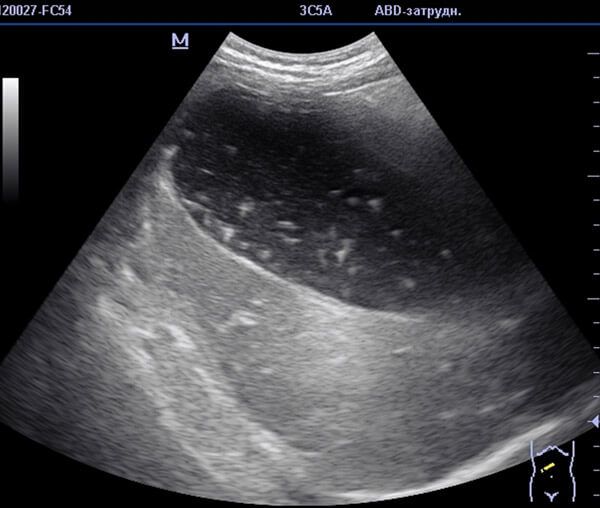

На фото УЗИ снимок, где диагностируется застой желчи в желчном пузыре.

Благодаря инструментальным методам диагностики получается визуальная картина печени, желчного пузыря, протоков и желудка. В результате инструментальной диагностики врач может обнаружить закупорку протоков, оценить степень поражения внутренних органов, задействованных в транспортировке желчи.

В качестве инструментальной диагностики применяются:

- УЗИ;